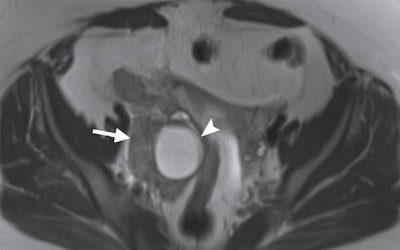

MRI of a 31-year-old woman with a ruptured hemorrhagic ovarian cyst and false-positive interpretation for acute appendicitis. Axial single-shot T2-weighted image shows a right ovarian cyst (above, arrowhead) with complex material along the lateral margin of the cyst (arrow). In retrospect, axial single-shot T2-weighted MRI shows a nonfluid-filled appendix (below, arrow) and no inflammation in the periappendiceal soft tissues. The patient underwent subsequent surgery. Images courtesy of Radiology.When Petkovska and colleagues analyzed the results by reader type, they found that attending physicians were slightly more accurate than radiology residents in their preliminary overnight MRI interpretations. However, the difference was not significant.